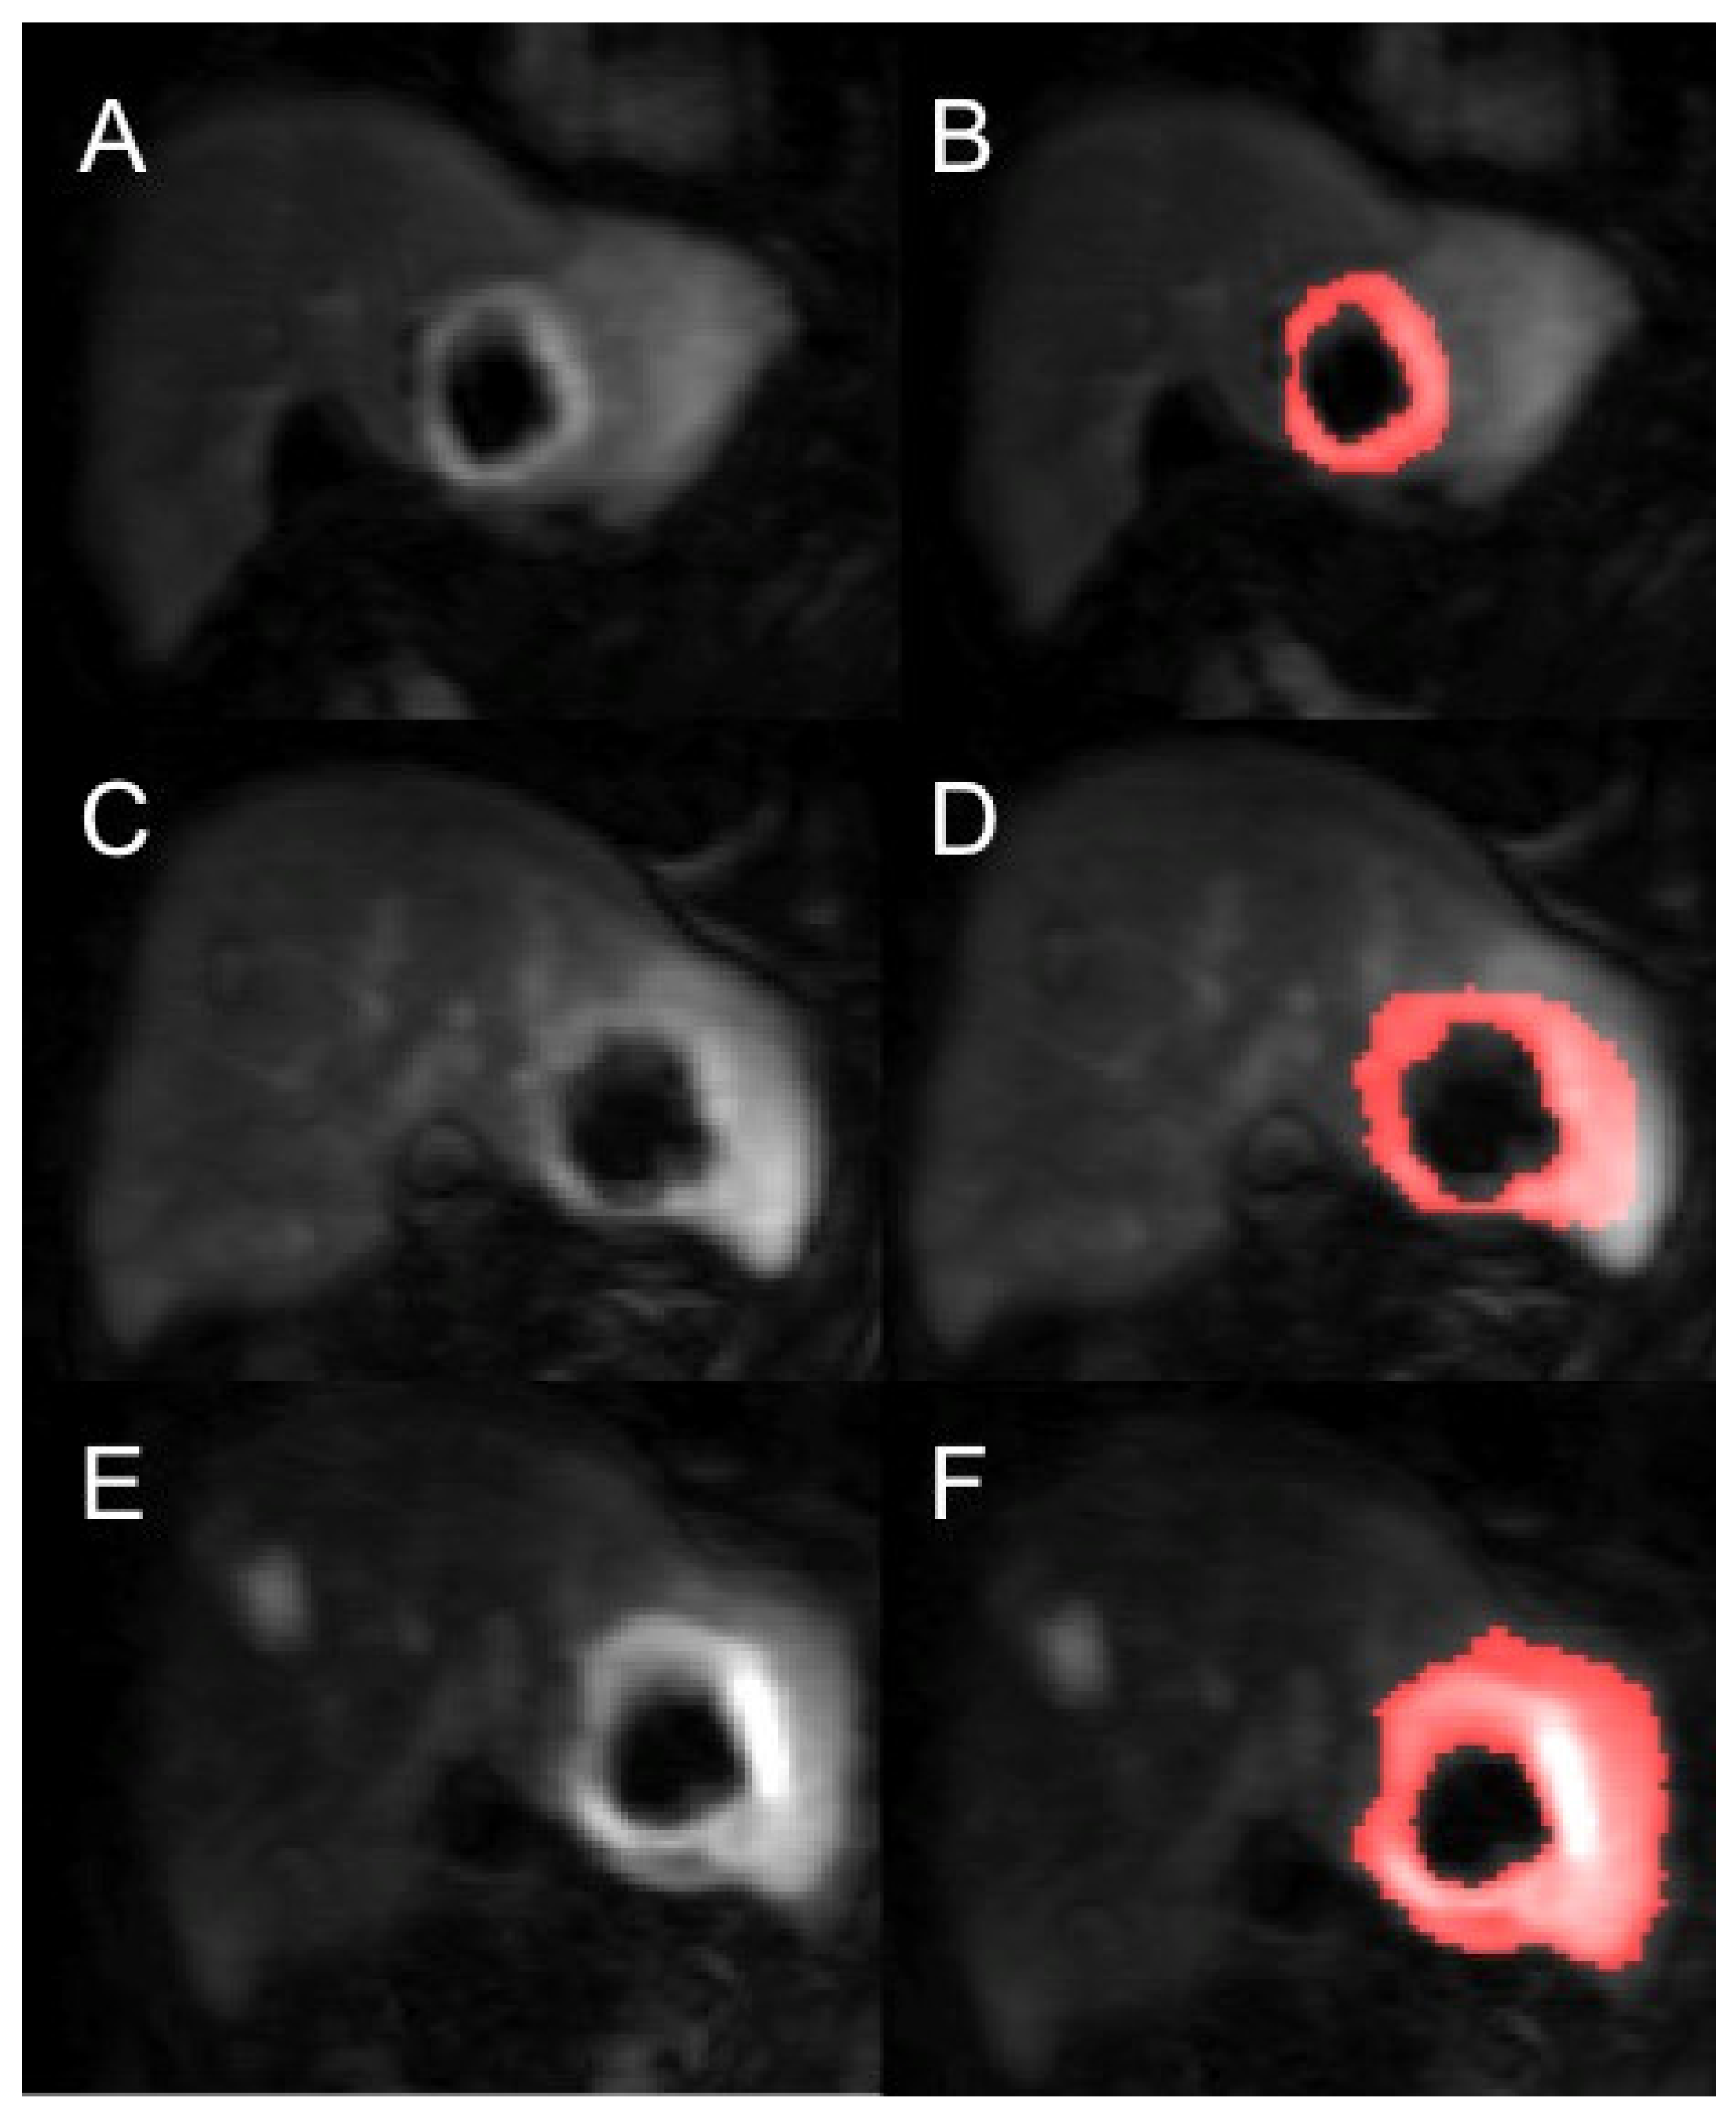

Contrast-agent concentration-time curves were approximated using relative change in signal (compared to baseline) against time [15]. Both readers examined all the MRI datasets (T1 and T2-weighted volumes as well as the post-contrast dynamic data) to help locate the tumours. To assist in identifying the perfused tumour and drawing the perfused tumour ROI, a map of maximum contrast agent concentration was generated. Using the map, tumour ROIs were drawn to encompass the entirety of the perfused tumour, non-enhancing areas and surrounding peri-tumoural tissue. This was done on each image slice that the tumour was present in to generate a 3-dimensional ROI. Using a percentage thresholding technique, the perfused renal tumour volume was more accurately selected to avoid the most peripheral voxels of the lesion to avoid partial volume effects. Using this method, only the perfused tumour was analysed rather than surrounding normal parenchyma or necrotic tissue. This was repeated for every measurable lesion on the DCE-MRI and for all three time points for each patient (Figure 2).

Figure 2. Example of a segmented renal metastasis on DCE-MRI within the left lobe of liver (before and after segmentation with thresholding technique of tumour ROI—the red highlighted area is the tumour ROI segmented on the PMI software) at baseline (A,B), 4-weeks (C,D) and 10-weeks (E,F). This is a case of disease progression at 6 months.